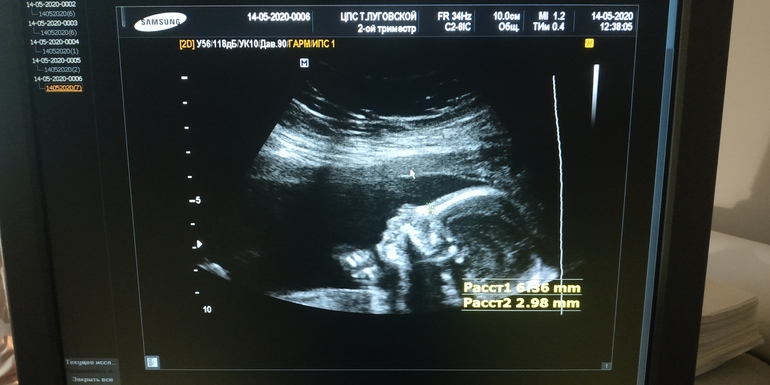

УЗИ, КТГ, доплерУвидела сегодня нашу красотульку на УЗИ 💕 она забилась в уголочек)) и сосала кулаки😆 и такая стесняшка, личико закрывала..) Лежит головой вниз.. Похожа снова не на меня🤣

Доктор папе сделал крупным планом фото причинного места😆 папа спокоен, что это точно девочка)

Всё у нас отлично, по срокам прям день в день как по месячным) так что ждём-с 22-23.09)))